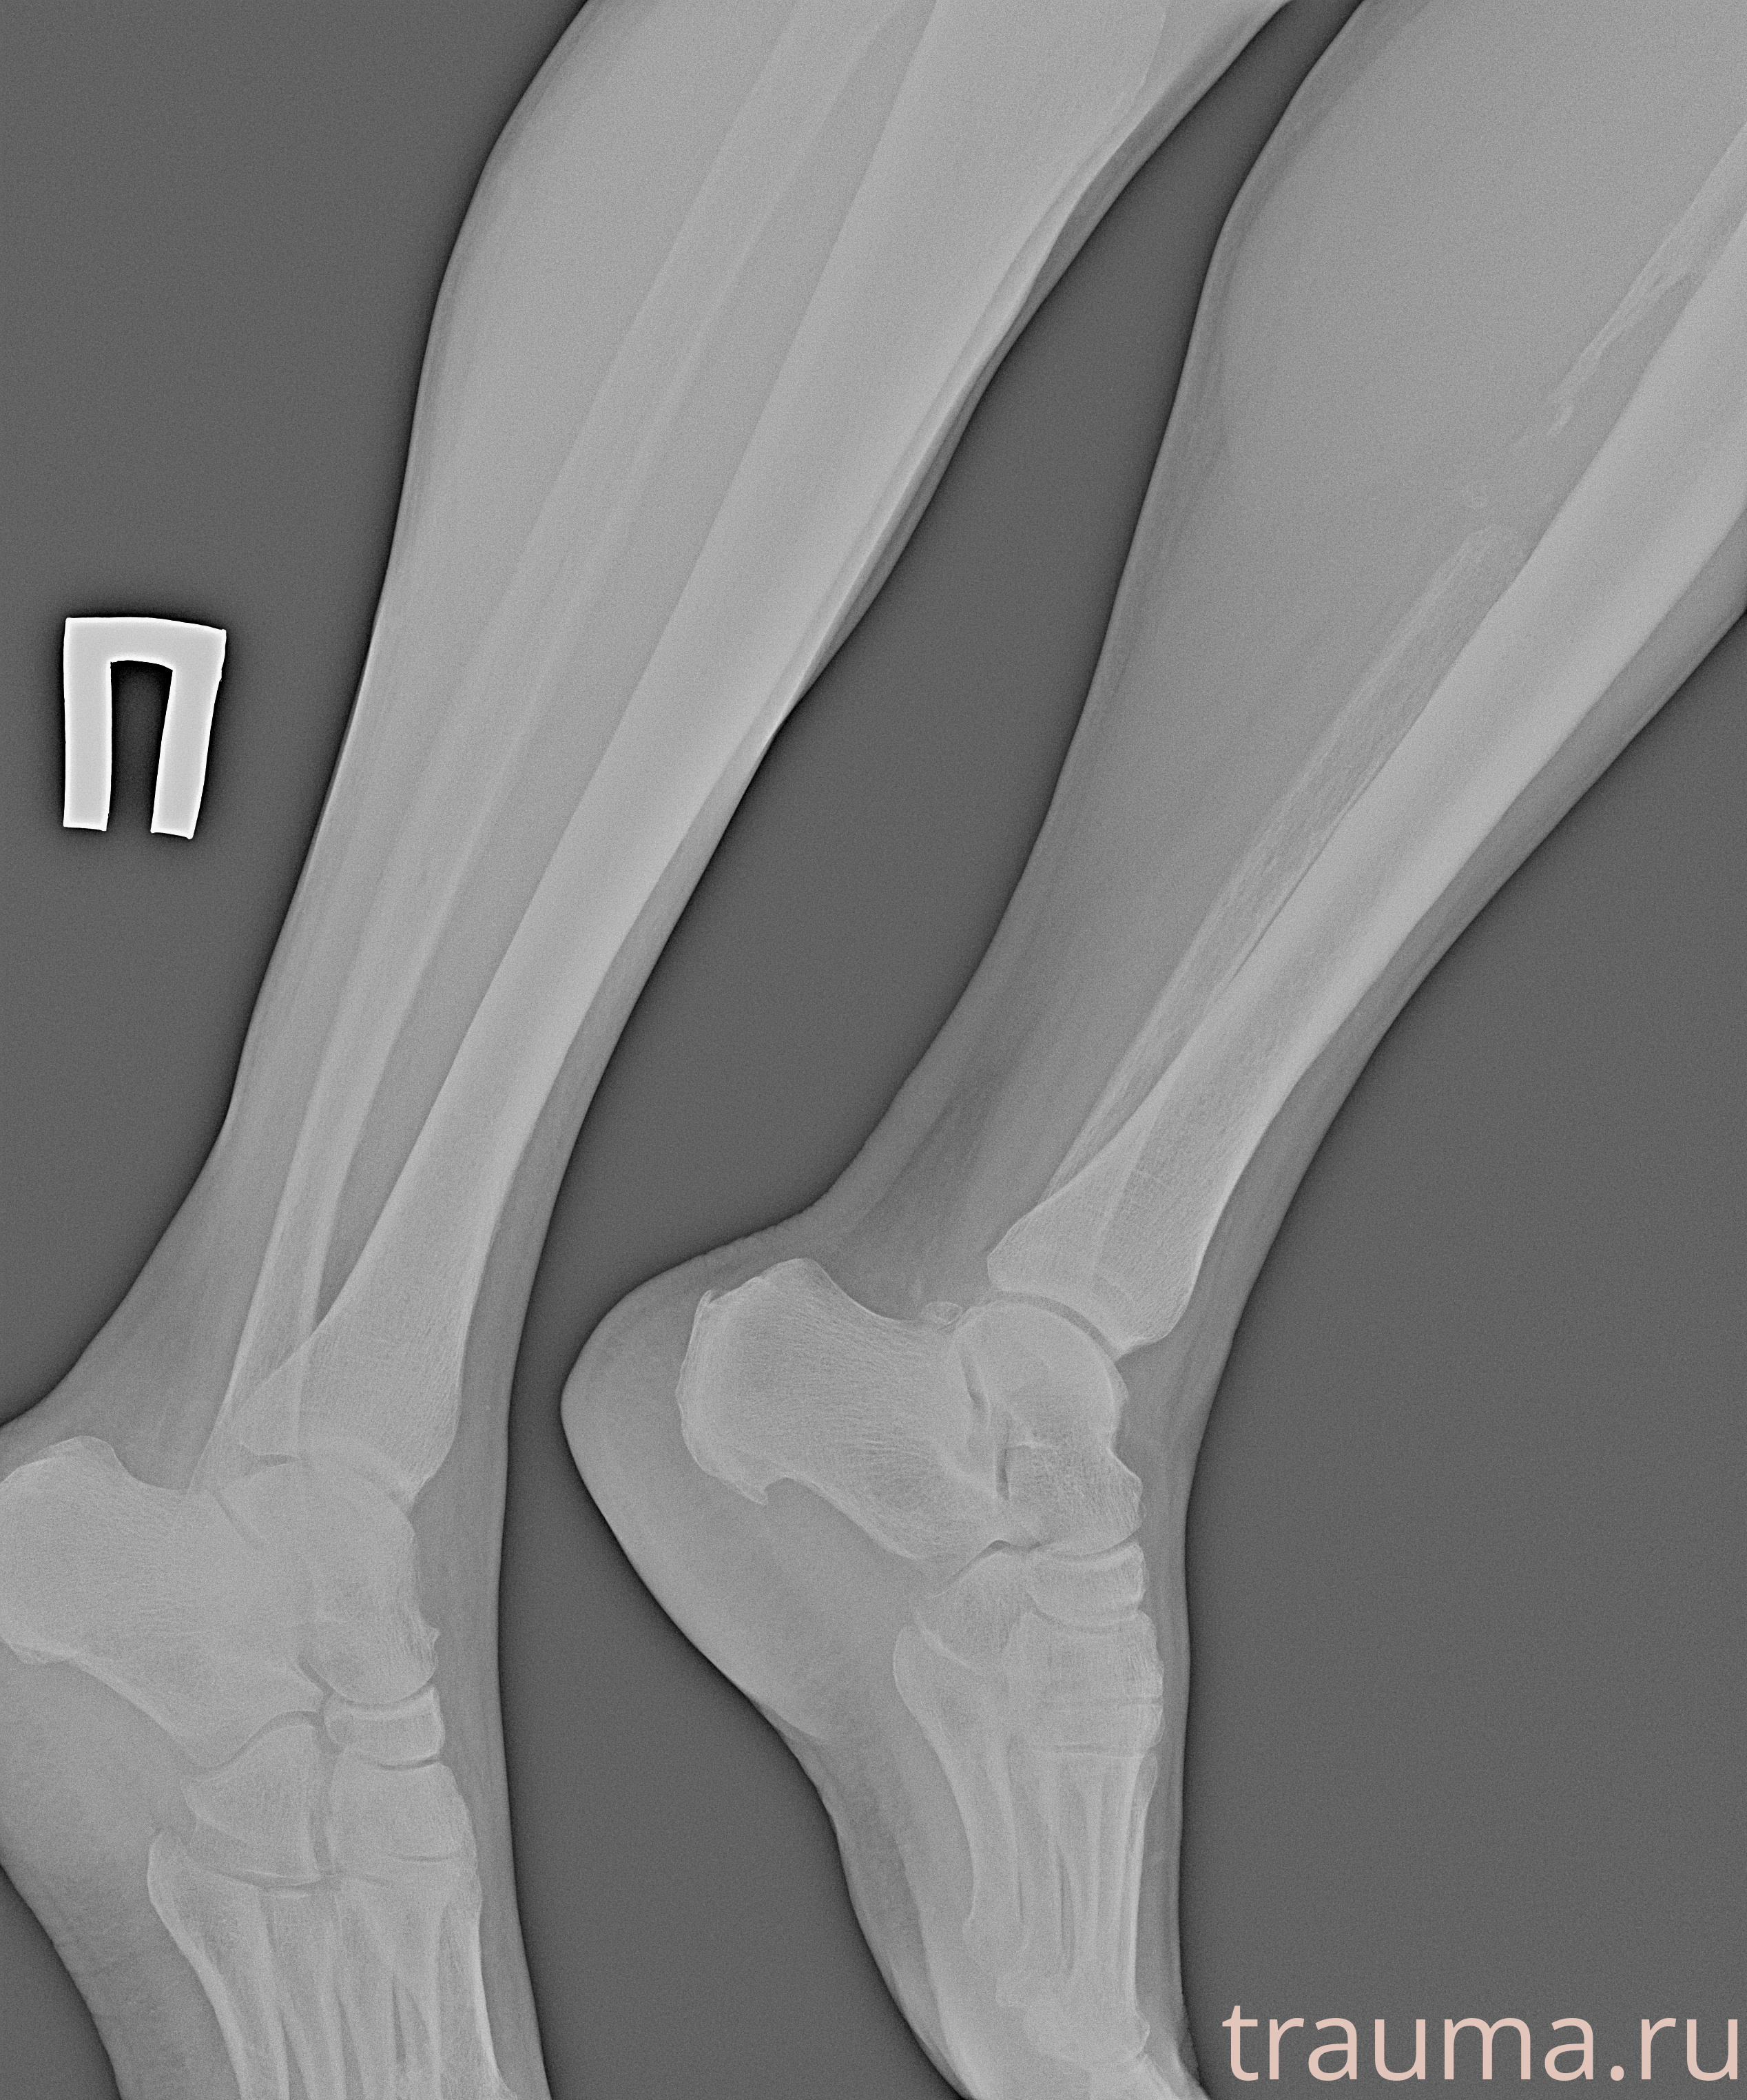

Рентгенограммы

Рентген на дому: по вашему адресу приезжает врач-рентгенолог, травматолог-ортопед с мобильным рентгеновским аппаратом, проводит диагностику травмы или заболевания, делает необходимые рентгенограммы, дает рекомендации по дальнейшему лечению. Получить качественные снимки в домашних условиях возможно благодаря уникальной методике, разработанной МосРентген Центром для института  Склифосовского

Яркость: 1   Контраст: 1   Инвертировать: 0 Увеличение: 1

Перетаскивайте мышь вверх/вниз для контраста, влево/право для яркости. Прокрутка колесом изменяет масштаб. Нажмите Сбросить для возврата к исходному изображению. При увеличении держите мышь в той области, которую хотите рассмотреть.